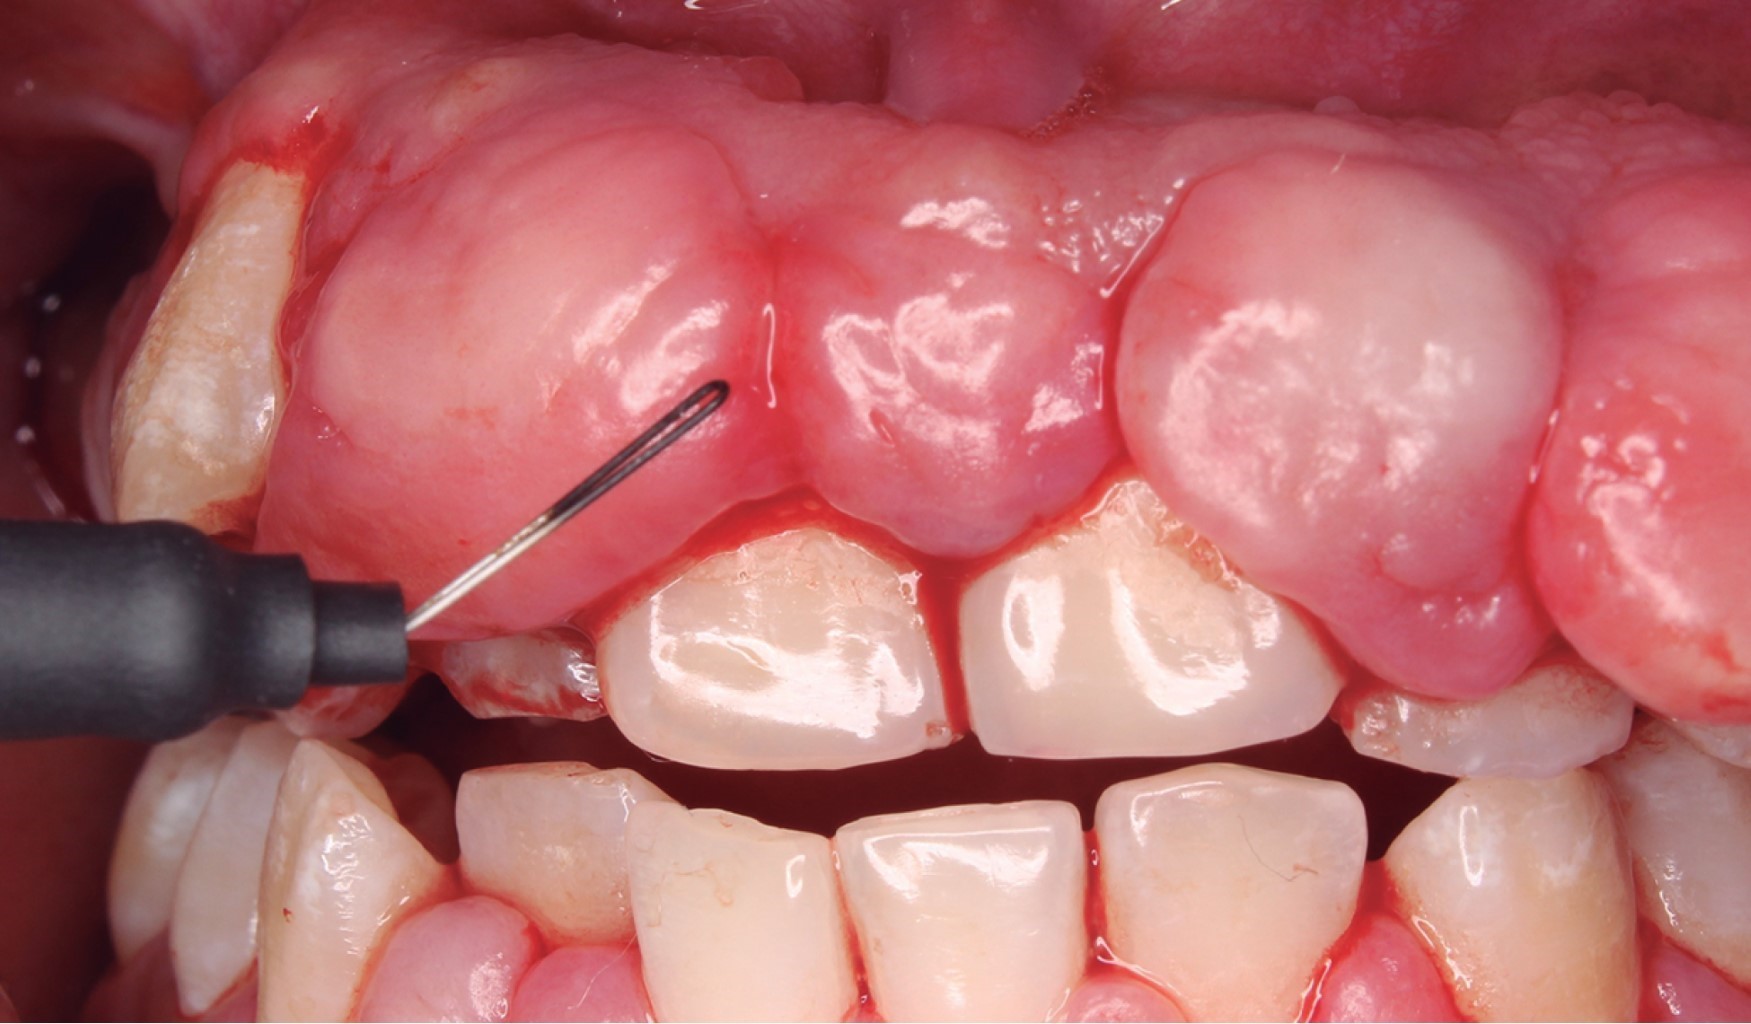

Se realizó la gingivectomía y gingivoplastia en ambos sextantes (Figura 3). Terminando el procedimiento quirúrgico se colocó una membrana de satín hemostático absorbible (Lides S-100) en la cara vestibular del sextante #2 (Figura 4). Se recetó amoxicilina de 500 mg cada ocho horas por siete días, ibuprofeno 600 mg cada ocho horas por cinco días, ketorolaco 10 mg cada ocho horas por cinco días, y enjuagues de clorhexidina al 12% con indicaciones al paciente y se le dieron citas de revisión (Figura 5).

Figura 3